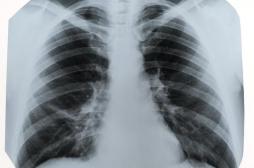

LES MALADIES

SYMPTÔMES